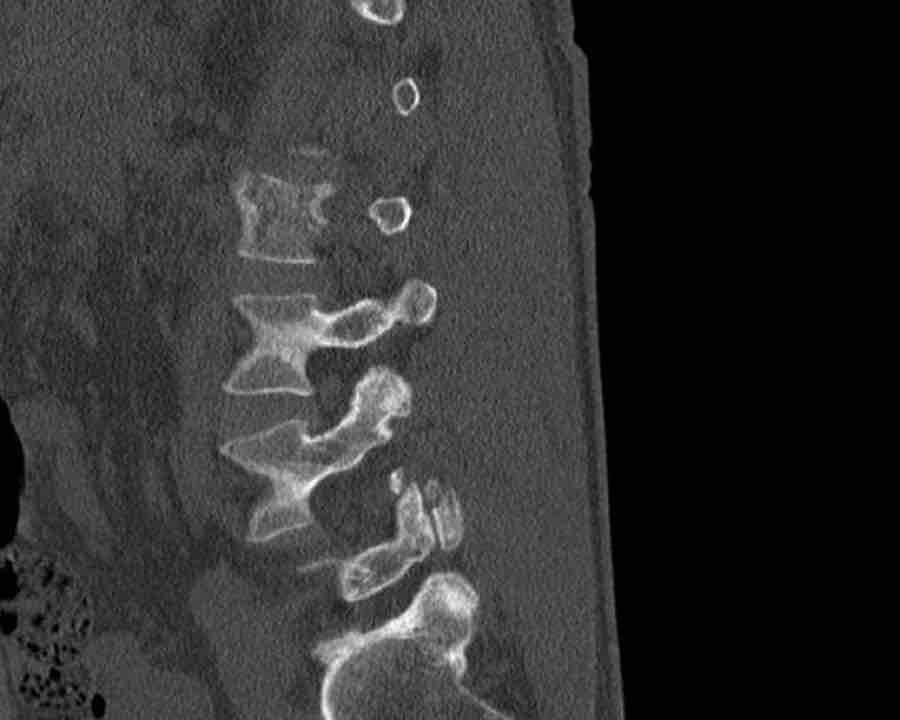

Here more examples of typical burst injuries.

Due to the axial force, the vertebral body is ‘split in half’, therefore a sagittal course of the fracture is common.

Therefore a fracture through the posterior osseous structures is possible in some type A injuries and should not always be regarded as a posterior distraction injury.

This can be confusing sometimes.